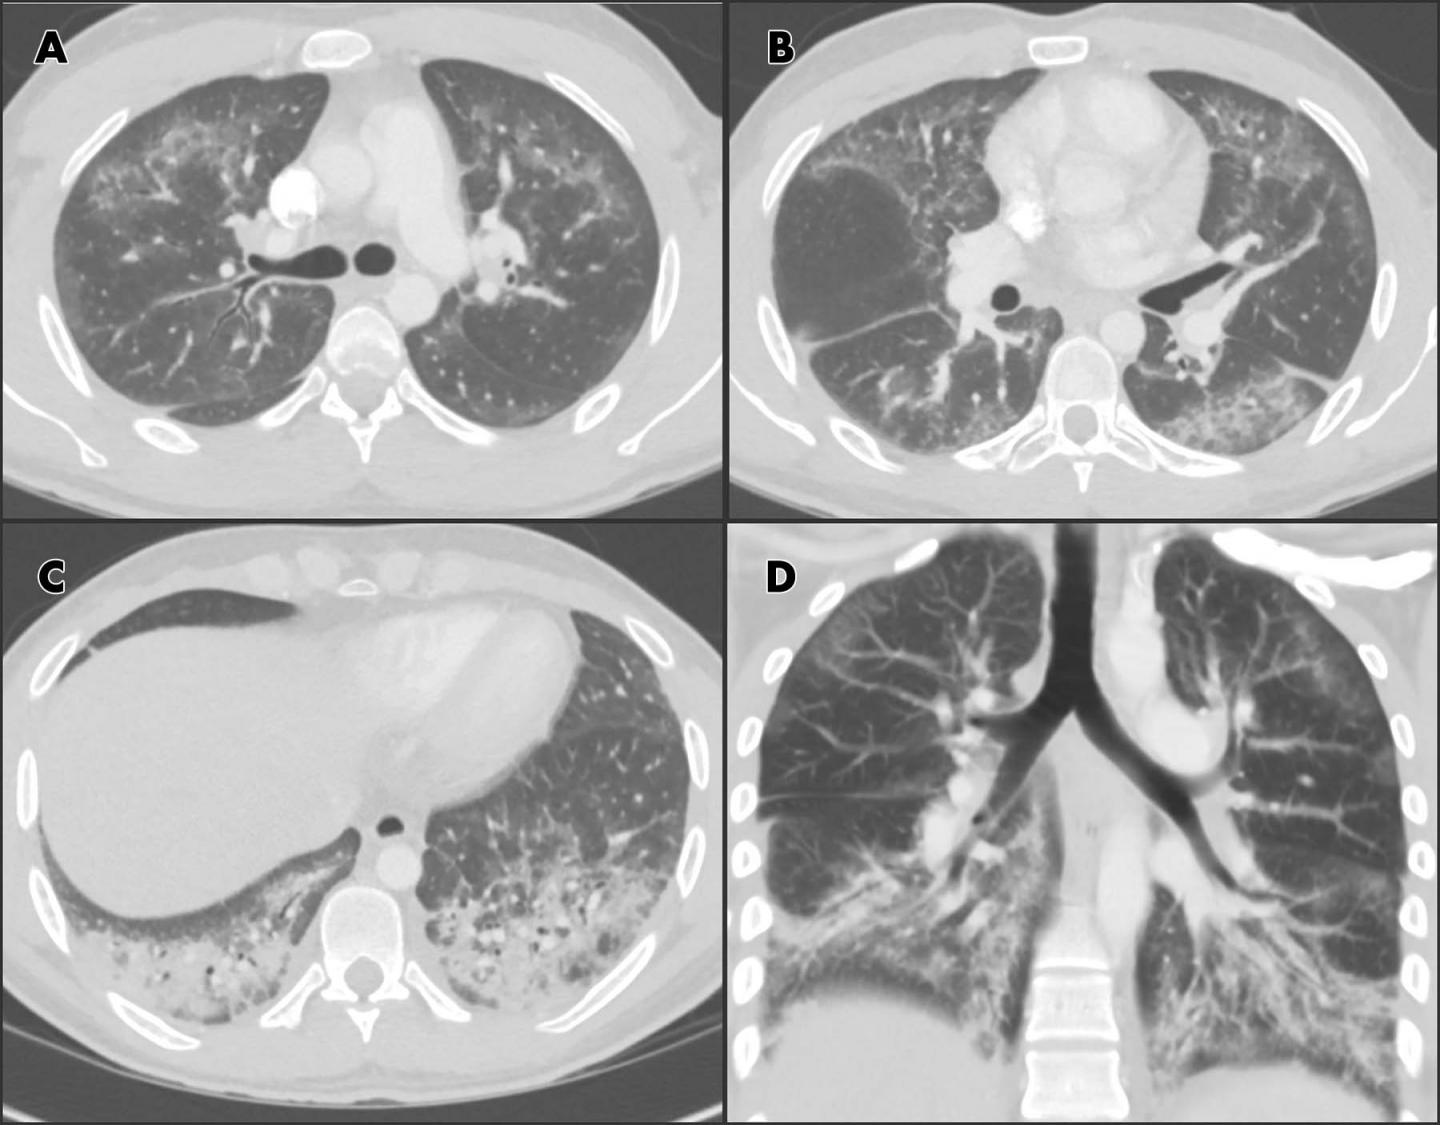

image: Chest CT angiographic images in a 24-year-old man with a history of e-cigarette use. A-C, Selected axial sections of the lung presented on lung windows reveal patchy ground-glass opacities distributed bilaterally with some, A, B, subpleural sparing and, C, consolidation in the lung bases. D, Coronal oblique thick-slab average intensity reconstruction shows the predominance of the findings in the basal lungs and demonstrates the peripheral subpleural sparing. view more

In the special report, Drs. Abbara and Kay summarize recent cases from the literature and illustrate some of the radiographic and CT findings of lung injury with a clinical case of a 24-year-old male patient with past medical history of asthma, who presented with shortness of breath, productive cough, chest pain and fever for one week. The patient reported current daily use of e-cigarettes (with tobacco) and marijuana, without substantial change in recent vaping habits. He had high white cell and platelet counts. His chest X-ray showed ground-glass and reticular, or netlike, opacities in both lungs.

CT findings included ground glass opacities and pulmonary consolidation with relative subpleural sparing. Histologic specimens obtained from the right lower lobe at biopsy were suggestive of lipoid pneumonia. The patient was given steroids with a presumptive diagnosis of lung injury associated with e-cigarette use.